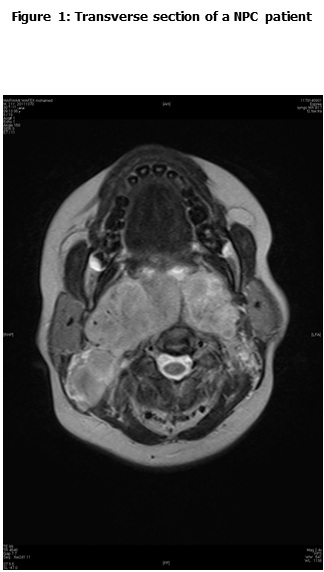

This is a retrospective study including all the newly diagnosed pediatric NPC who were diagnosed and treated at the Children Cancer Hospital Egypt (CCHE) during the period from July 2007 to December 2012. All imaging studies (e.g., CT or MRI scans) were reviewed by a senior head and neck radiologist for proper staging and assessment of tumor response. Patients were staged according to AJCC staging system. Modified version of the Response Evaluation Criteria in Solid Tumor (RECIST) was used to assess response.

This is a retrospective study including all newly diagnosed pediatric NPC at Children Cancer Hospital Egypt CCHE during the time period from July 2007 to December 2012. The patients' profiles were systematically reviewed for characteristics including pathology, laboratory, radiological work up and documented toxicities. All imaging studies (e.g., CT and MRI scans) were reviewed by a senior head and neck radiologist for proper staging and assessment of tumor response.

Pretreatment evaluation included a complete history and physical examination, complete blood count, serum biochemistry tests (including evaluation of electrolyte levels, hepatic and renal function tests), CT or MRI scans of the head and neck region, chest and bone scan. During therapy weekly examinations and laboratory evaluations were performed. Tumor response was assessed by clinical examination with appropriate MRI imaging studies after completion of neoadjuvant chemotherapy and at the end of radiotherapy.

The most common presentation was dysphagia seen in 23 patients (88.5%), followed by cervical lymphadenopathy in 21 (80.8%), and symptoms of increased intracranial pressure in 19 (73%) patients. The T1, T2, T3 and T4 tumor size was presented in 2 (7.7%), 5 (19.2%), 8 (30.8%) and 11 (42.3%) patients respectively. N0, N1, N2 and N3 was detected in 1 (2.8%), 8 (30.8%), 16 (61.5%) and 1 (3.8%) patients respectively. Three patients (11.5%) were metastatic at presentation.